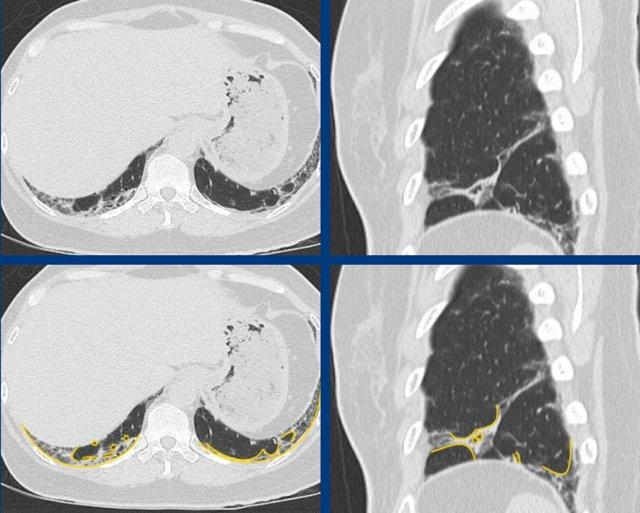

Ở bệnh nhân có xơ hóa ưu thế vùng đáy và dưới màng phổi, không có các đặc điểm phụ trợ không phù hợp, sự hiện diện hay vắng mặt của tổ ong sẽ quyết định việc phân loại là dạng UIP xác định hay có thể.

Tổ ong trên hình ảnh CT được định nghĩa là “các khoang khí dạng nang tập hợp theo hướng dưới màng phổi, thường có kích thước khoảng 3-10 mm”.

Trong A có hình ảnh tổ ong kết hợp với xơ hóa ưu thế ở nền phổi và dưới màng phổi, cho thấy hình thái UIP điển hình.

In B there is a probable UIP pattern without honeycombing.

The ongoing process of honeycombing formation. There is a spectrum ranging from normal lung tissue (A), through distortion of the secondary lobule with traction bronchiolectasis (B), to end stage cyst formation (C).

Tổ ong

là kết quả của xơ hóa tiến triển kèm theo biến dạng cấu trúc và nằm ở cuối thang điểm từ mô phổi bình thường, qua biến dạng tiểu thùy thứ cấp với giãn phế quản nhỏ do co kéo, đến hình thành nang giai đoạn cuối.